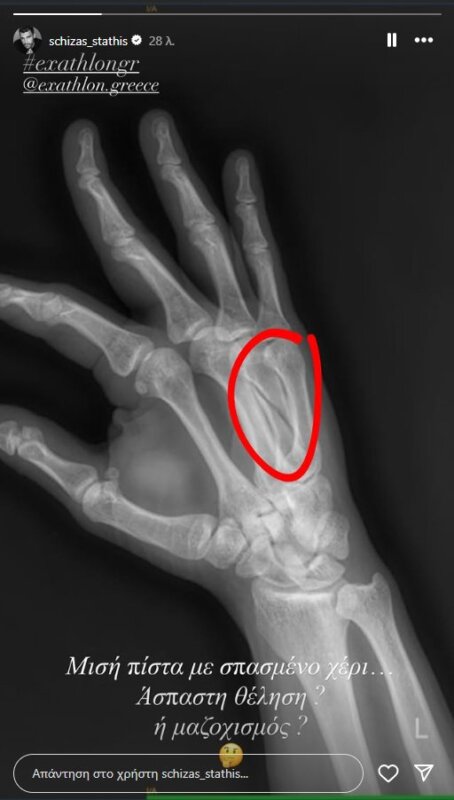

Ο Αγρινιώτης Στάθης Σχίζας έσπασε το χέρι του στον αγώνα που προβλήθηκε την 6η Σεπτεμβρίου και αποχώρησε οικειοθελώς από το «Exathlon».

Δευτερόλεπτα αφού επισημοποιήθηκε η αποχώρησή του ανέβασε στο Instagram post με την ακτινογραφία που έβγαλε και δείχνει ξεκάθαρα το τι ακριβώς έχει συμβεί.